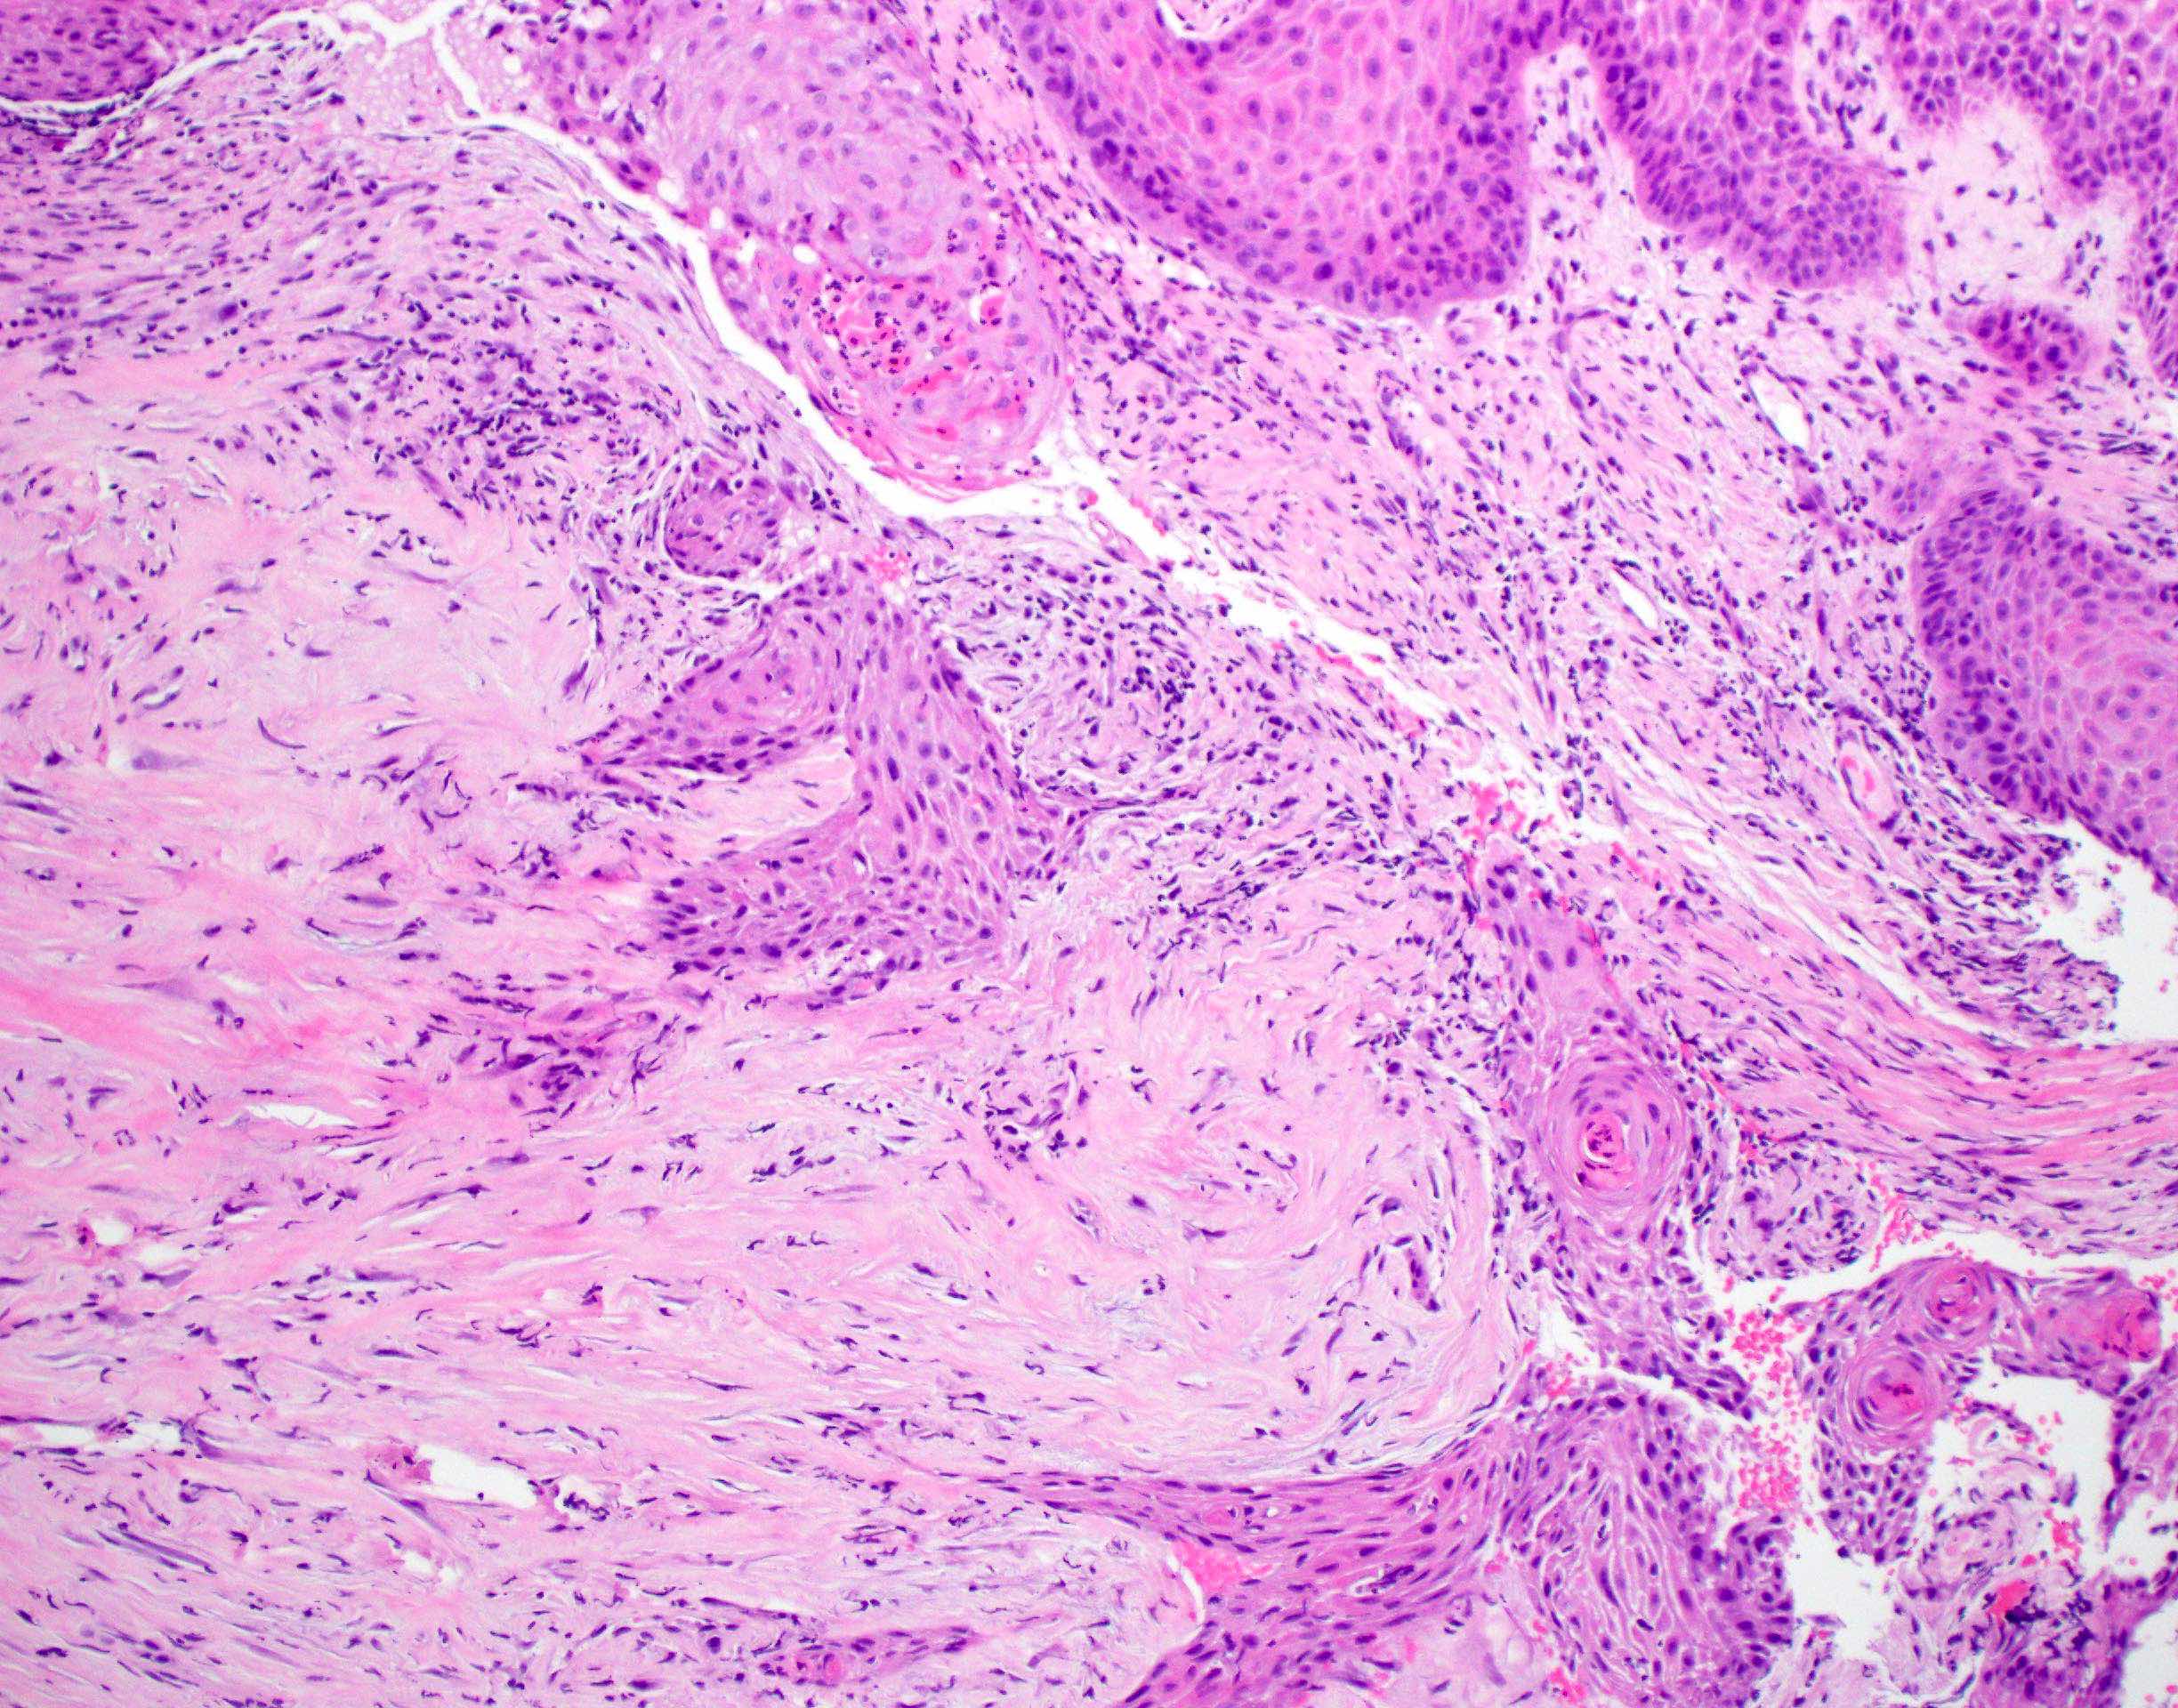

- Squamous cell carcinoma, conventional

- Most common and typical morphology of conventional keratinizing squamous cell carcinoma at any site

- Large polygonal malignant cells with intercellular bridges

- Cytoplasmic or extracellular eosinophilic keratin

- Dyskeratotic cells and squamous pearls

- Nuclear size, pleomorphism, hyperchromasia and mitoses increase with increasing grade